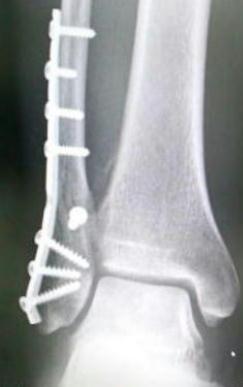

• 適当な板を骨に沿わせてネジ止めするという、治療と言うよりは全くの大工仕事。<br />

適当な板を骨に沿わせてネジ止めするという、治療と言うよりは全くの大工仕事。

でも、MRI画像よりレントゲン写真のほうがリアリティが。

暖かみもあるし。